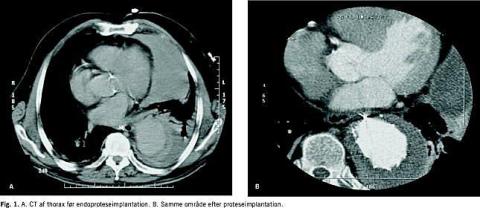

En 78-årig mand, der tidligere var blevet opereret for infrarenalt abdominalt aortaaneurisme, blev indbragt til et lokalt sygehus grundet akutte abdominale smerter og kredsløbsshock. Ved ankomsten var patientens blodtryk 80/50 mmHg, og han var påvirket af smerter i epigastriet. På mistanke om rumperet abdominalt aortaaneurisme blev patienten overflyttet til karkirurgisk afdeling. Ved en UL-undersøgelse kunne abdominalt aneurisme ikke påvises, men der fandtes en stor venstresidig pleural ansamling. Ved en CT diagnosticeredes et rumperet 10 cm bredt og 12 cm langt aneurisme i aorta thoracica descendens med blødning og venstresidig hæmotorax (Fig. 1A ). Aneurismet fandtes at være tilgængeligt for endovaskulær terapi. Umiddelbart herefter blev der i lokal analgesi foretaget kirurgisk fremlægning af a. femoralis og implantation af tre selvekspanderende endoproteser (Talent, Medtronic AVE, USA), som blev placeret overlappende hinanden i aorta. En kontrolarteriografi viste eksklusion af aneurismet. Det endovaskulære indgreb varede 30 minutter, hvorefter den venstresidige massive hæmothorax blev dekomprimeret for 1 liter blod. Det postoperative forløb var ukompliceret. Ved kontrol efter fire måneder fandtes patienten at være velbefindende, og en CT viste, at der var tæt endoprotese, og at aneurismet var skrumpet ( Fig. 1 B ).